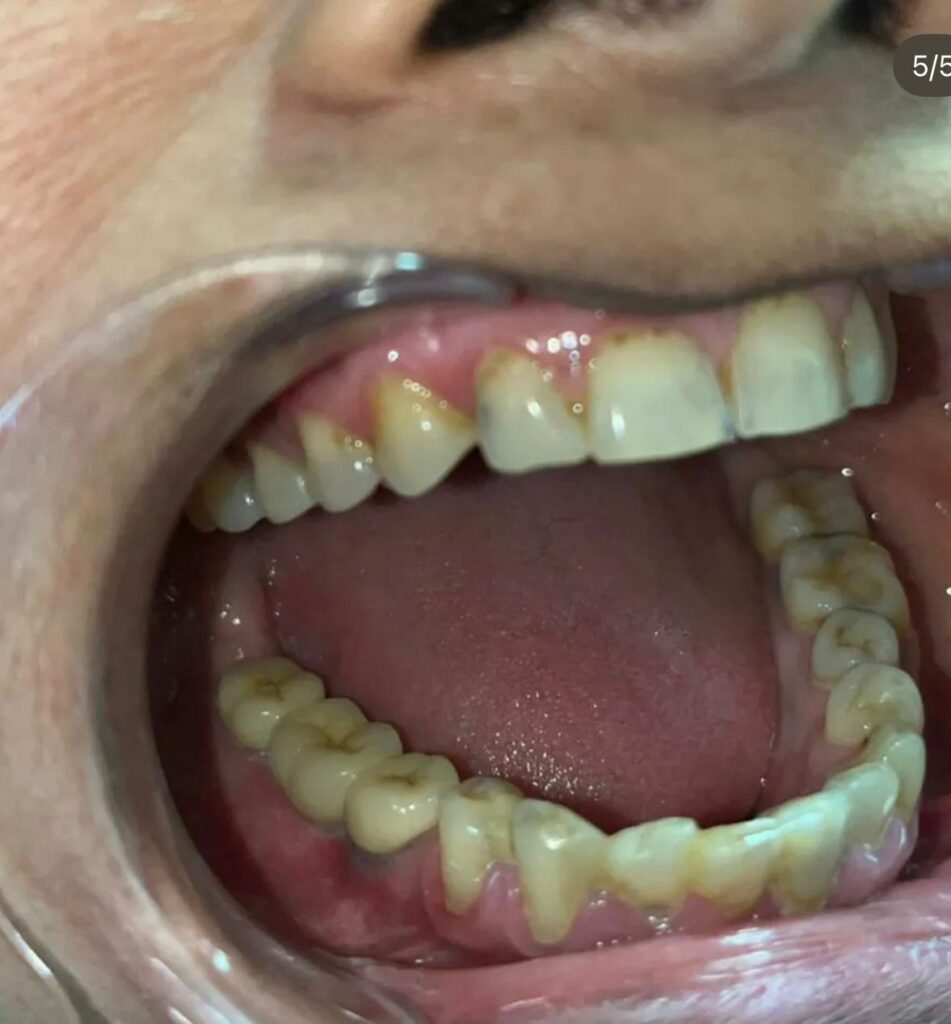

Dental implants are permanent solutions for missing teeth, where titanium posts are placed into the jawbone to support artificial teeth. Full mouth implants replace all missing teeth, restoring complete function, aesthetics, and confidence with natural-looking results.

Full mouth implants are ideal for patients with multiple missing teeth, providing a fixed, stable, and comfortable solution compared to traditional dentures.